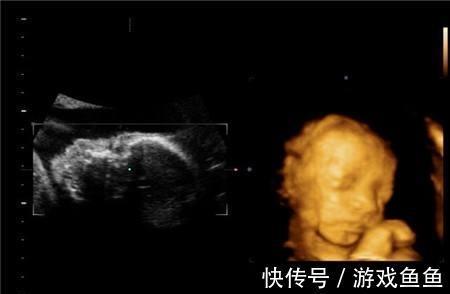

文章插图